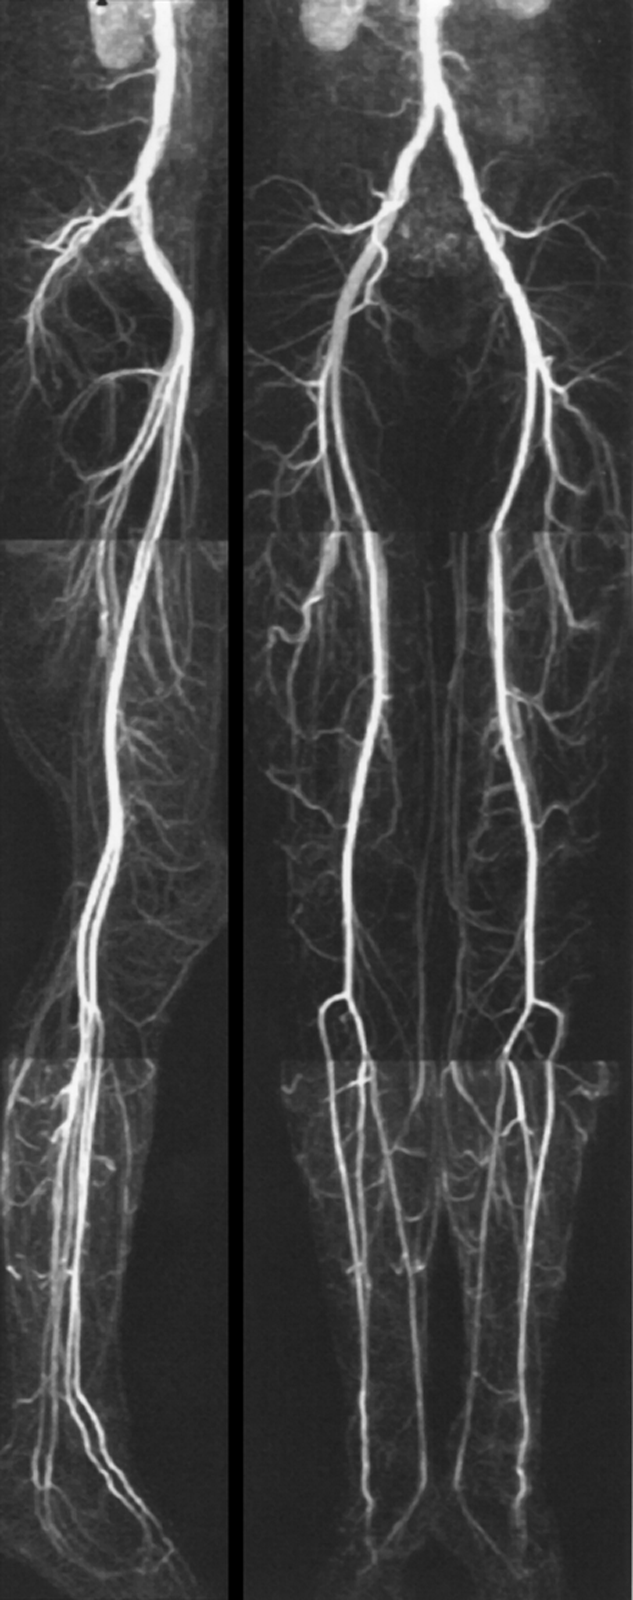

In combination with mechanical de­vi­ces the entire peripheral vascular system can thus be examined after a single contrast agent injection (Fi­gu­re 14-22). The com­bi­­na­tion of ra­­pid automatic table movement and automatic injection and follow-up of the bolus allows mul­ti­ple suc­ces­si­ve acqui­sitions.

Figure 14-22:

Moving-bed CE-MRA of the pelvis and legs.